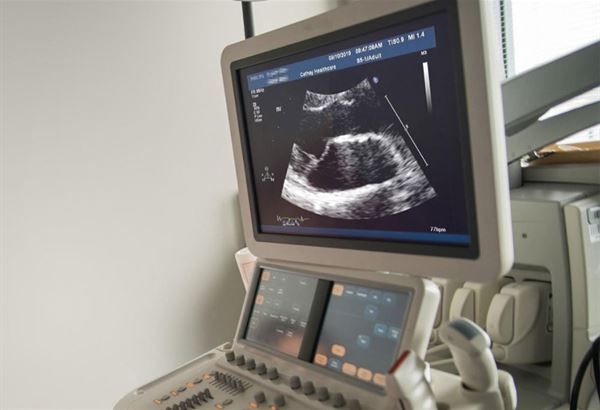

●心臟超音波檢查:看心臟結構與功能、瓣膜情況

接下來是透過心臟超音波,主要可以看到心臟結構與功能、瓣膜情況等,像二尖瓣膜脫垂,或血管阻塞造成心臟運動情況異常,臨床醫師或健檢時藉由心臟超音波看出心臟是否健康的端倪。